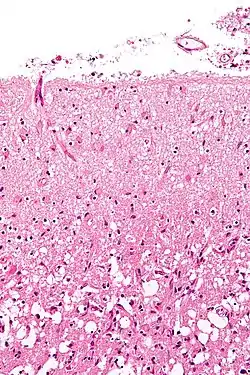

Formation of reactive astrocytes after central nervous system (CNS) injury | |

Astrogliosis (also known as astrocytosis or referred to as reactive astrogliosis) is an abnormal increase in the number of astrocytes due to the destruction of nearby neurons from central nervous system (CNS) trauma, infection, ischemia, stroke, autoimmune responses or neurodegenerative disease. In healthy neural tissue, astrocytes play critical roles in energy provision, regulation of blood flow, homeostasis of extracellular fluid, homeostasis of ions and transmitters, regulation of synapse function and synaptic remodeling.[1][2] Astrogliosis changes the molecular expression and morphology of astrocytes, in response to infection for example, in severe cases causing glial scar formation that may inhibit axon regeneration.[3][4]